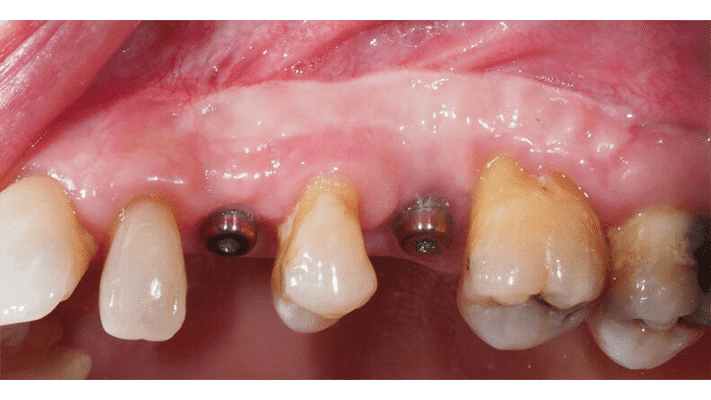

Cette rubrique est la retranscription d'un échange entre les Drs Olivier Samtmann et Erwan Hauchard sur leur cas clinique de vestibuloplastie.

Erwan Hauchard : Waouh, les résultats sont impressionnants ! Et tout cela sans substituts ! Mais penses-tu que l'on puisse obtenir des résultats similaires dans tous les types de reconstructions ?

Olivier Samtmann : C'est une excellente question (rires)... L'épaisseur de tissu kératinisé obtenue dépendra de l'épaisseur du tissu colonisé. En toute franchise, cette analyse ne se base que sur mon expérience personnelle, mais les reconstructions osseuses entraînant une couche importante de pseudo-périoste sont celles où cette technique sans substitut donnera le meilleur résultat. Il s'agit essentiellement de reconstructions avec utilisation de biomatériau (type os bovin anorganique) et/ou avec usage de dispositifs de maintien non résorbables (membrane PTFE ou grille...